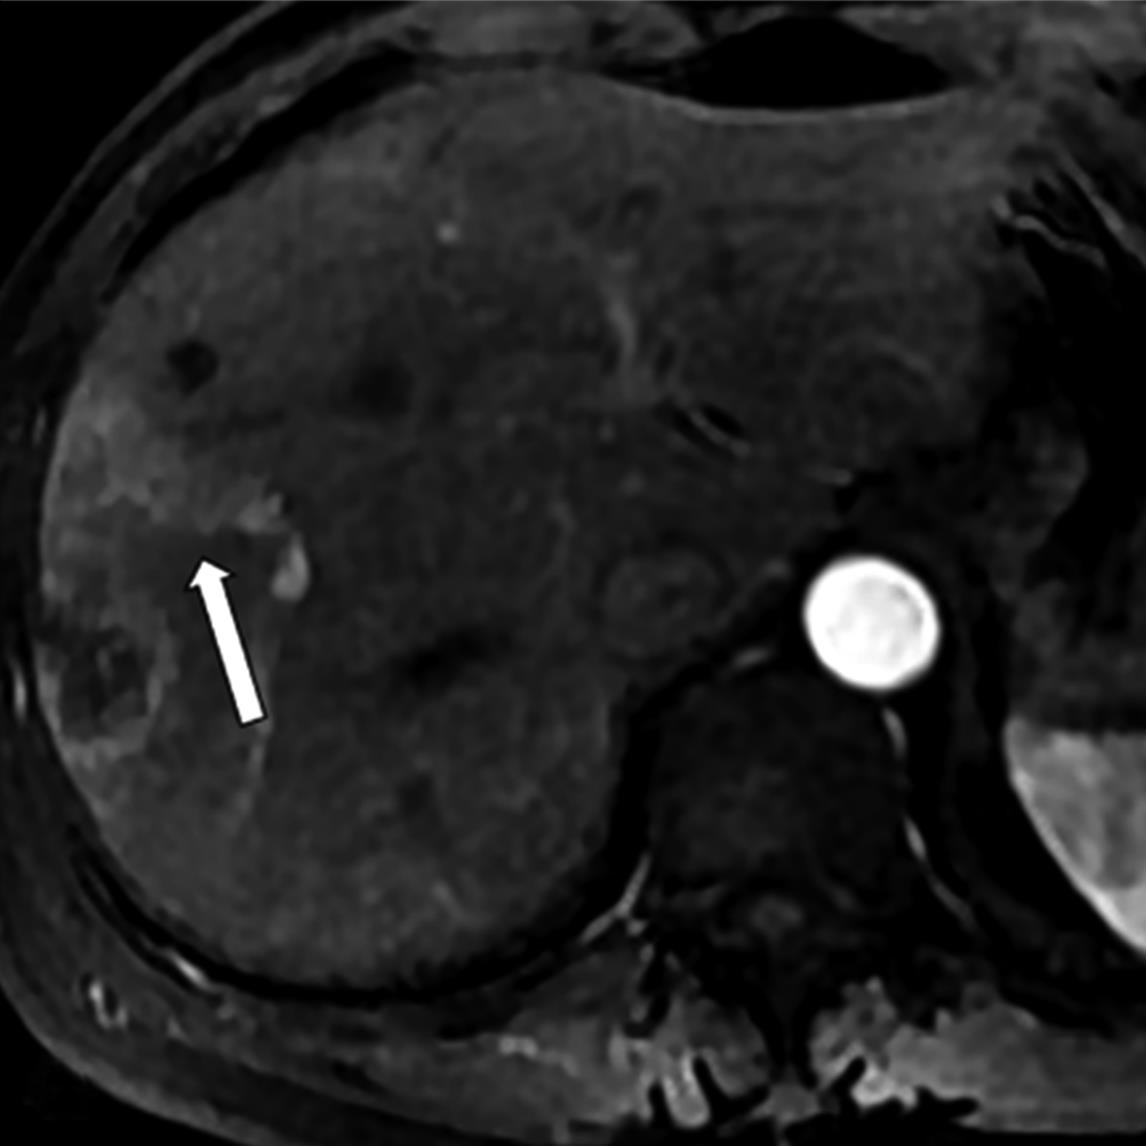

• MRI瘤周特征在预测结直肠癌肝转移非解剖性肝切除术预后的价值

2023, 48(5):548-553. DOI: 10.13406/j.cnki.cyxb.003234

摘要 (129) HTML (25) PDF 780.46 K (241) 评论 (0) 收藏

摘要:目的 研究结直肠肝转移(colorectal liver metastases,CRLM)瘤周影像特征在非解剖切除(non-anatomic resection,NAR)后CRLM患者中长期预后的价值。方法 回顾性纳入术前行腹部钆塞酸二钠增强磁共振成像(magnetic resonance imaging,MRI)和NAR术后的CRLM患者。影像特征评估动脉期瘤周高强化、肝胆期(hepatobiliary phase,HBP)瘤周低摄取和瘤周胆管扩张。应用Kaplan-Meier法计算生存率,并采用Cox比例风险回归模型进行单因素和多因素分析以确定无肝内复发生存期(liver recurrence-free survival,LRFS)、无复发生存期(recurrence-free survival,RFS)和总生存期(overall survival,OS)的独立预测因素。结果 本研究共纳入36例患者,58个CRLM病灶。存在和不存在动脉期瘤周高强化的患者3年LRFS和RFS率有统计学差异(LRFS:14.3% vs. 43.9%,P=0.005;RFS:14.3% vs. 40.3%,P=0.006)。动脉期瘤周高强化与较差的LRFS(P=0.002,HR=5.541,95%CI=1.853~15.975)和较差的RFS(P=0.002,HR=5.392,95%CI=1.887~15.412)独立相关。胆管扩张和HBP瘤周低摄取均不为LRFS、RFS和OS的独立预测因素。结论 动脉期瘤周高强化是接受NAR的CRLM患者LRFS和RFS预后因子。